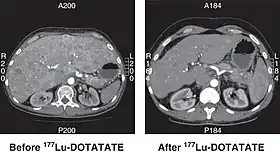

![]() CT scan of non-functioning pancreatic NET before and 6 months after successful treatment with four cycles of 177Lu-DOTATATE. | |